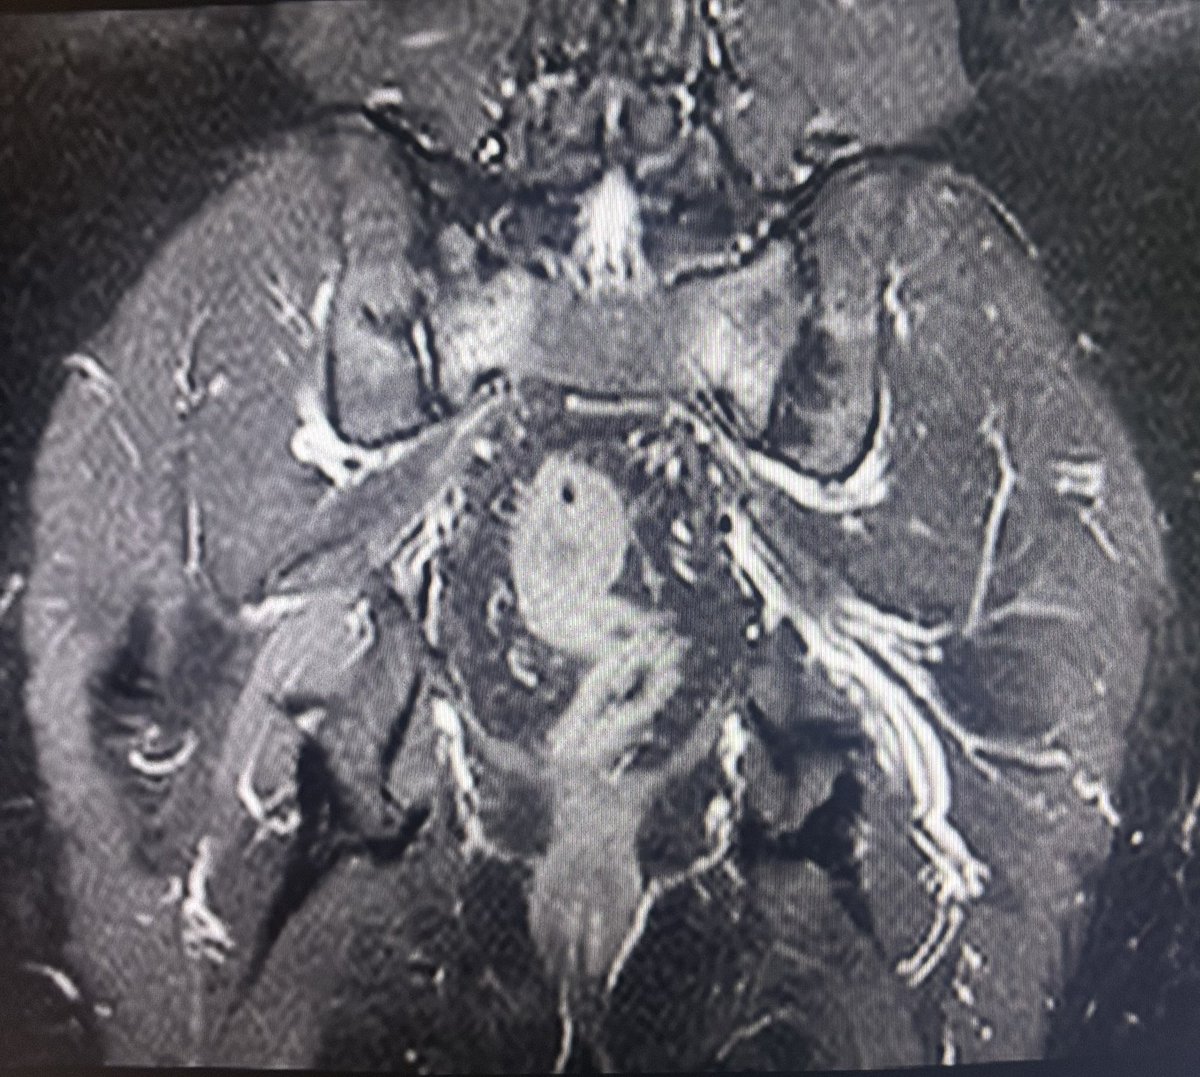

Is every edema along the SI joint Sacroiliitis?

This is a case of 45y/M came for follow up of Sacroiliitis which was reported elsewhere on an MRI 6 months back. What do we see here in addition to marrow edema?

Follow 🧵 for more.

#OrthoRad

#MSKimaging